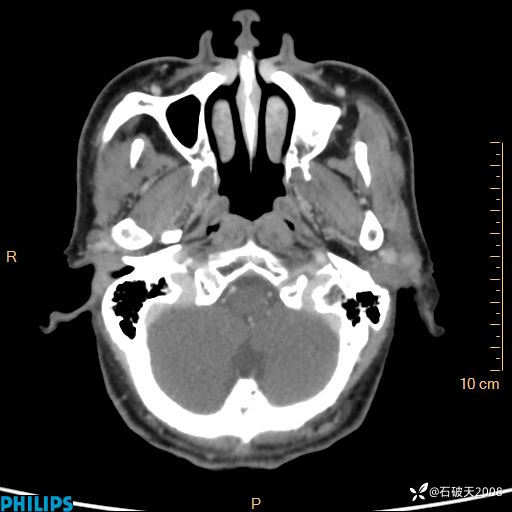

动脉期